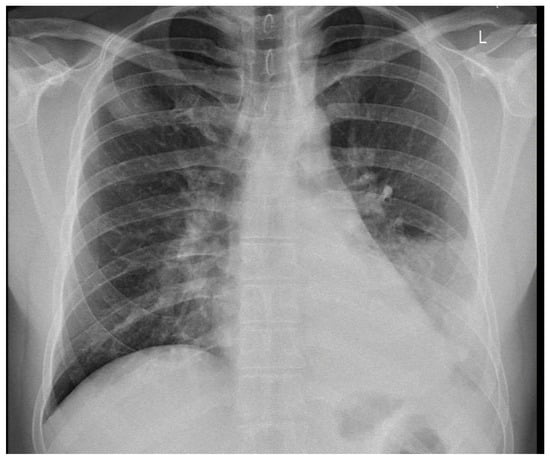

On August 27th, the patient again presented to an outpatient clinic because of stabbing pain on the left side of the chest. Information about the second hospitalization is available in Table 3. Due to a dull percussion sound over the left lung, a chest X-ray was taken and revealed fluid in the left pleural cavity reaching the third rib (Figure 5). The patient was readmitted to the hospital. On admission, a slightly elevated C-reactive protein level (11.51 mg/L) and a normal procalcitonin level (0.036 ng/mL) were found. Empirical intravenous antibiotic therapy with ceftriaxone (2 g per day for 10 days) and amikacin (500 mg twice per day for 10 days; used in addition to a broad-spectrum beta-lactam because of suspected bacteremia and broad-spectrum activity against Gram-negative bacteria) was implemented.

Figure 5. Chest X-ray during second admission to the ward revealed fluid in the left pleural cavity reaching the third rib.